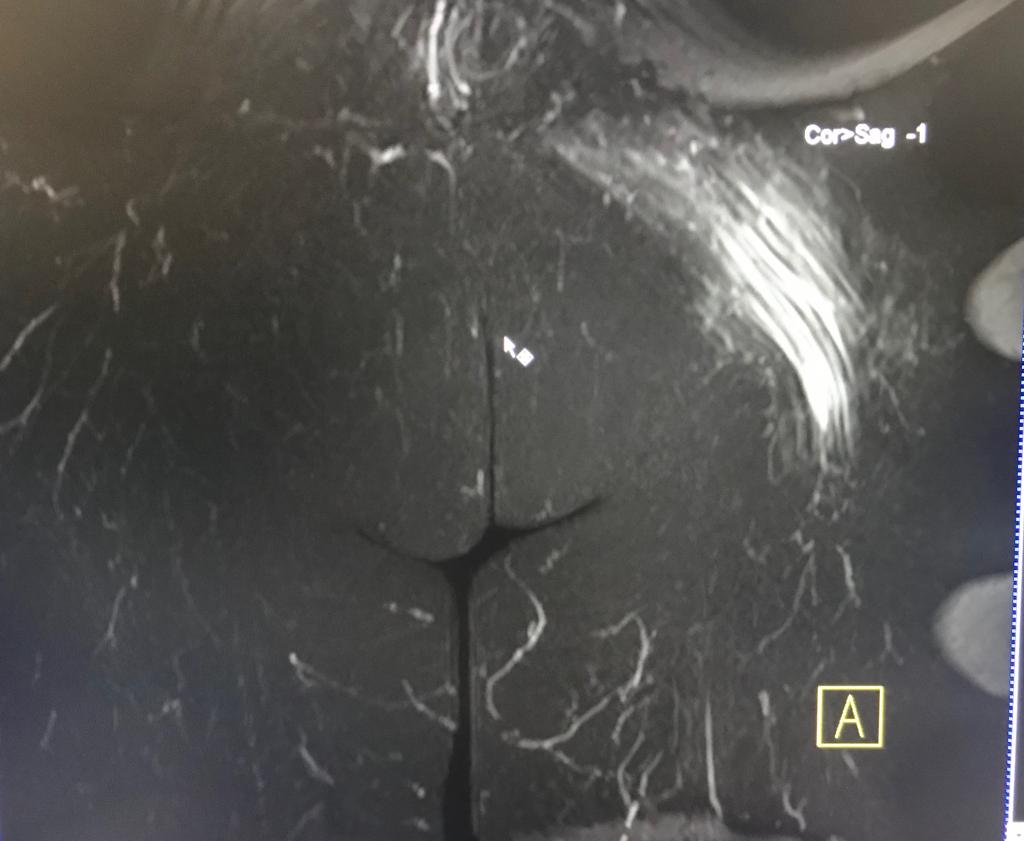

La RM es esencial para el diagnóstico de la topografía, severidad y extensión de los desgarros musculares.

Un compromiso fibrilar mayor del 15% del área muscular con una longitud superior a los 13cm y una localización central al vientre muscular , presenta un peor pronóstico y mayor tiempo de rehabilitación.

Un diagnóstico temprano es fundamental para evitar la retracción muscular y la formación de tejido cicatrízal.